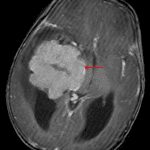

- Avidly enhancing mass with lobulated contours centered in the temporal horn of the right lateral ventricle measuring 6.5 x 5.5 x 6 cm, inseparable from the choroid plexus

- Adjacent parenchymal edema, particularly in the right temporal lobe, which may relate to tumor invasion or subependymal edema in the setting of hydrocephalus

- Tumor bulges into the adjacent cerebral parenchyma in multiple locations

- Cystic collections along the tumor margins may represent peritumoral cysts and/or isolated ventricular components

- Mild corresponding restricted diffusion

- Associated mass effect with 1.5 cm right-to-left midline shift, effacement of the third ventricle, and crowding of the basal cisterns with mass effect on the midbrain

- Dilation of the lateral ventricles consistent with obstructive hydrocephalus

Choroid plexus carcinoma